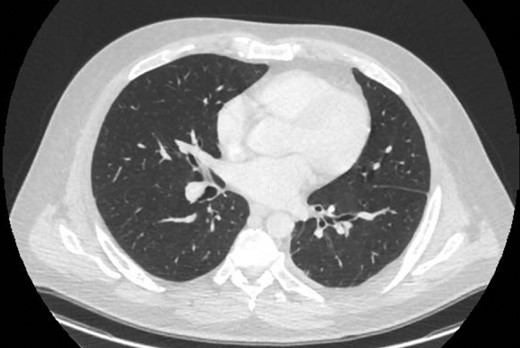

The operation was performed via mini-thoracotomy, finding an infected cavity, loculated fluid with pus flakes. No abnormal tract through the diaphragm was noted. The thick pleural rind was separated and the lung released with complete re-expansion. He was transferred to the ward with two drains. These were removed day four when the small air-leak resolved. Subsequent thoracic imaging showed complete re-expansion (Fig. 6).

CT one month post-decortication with complete re-expansion of the left lung and minor post-operative changes noted posteriorly.